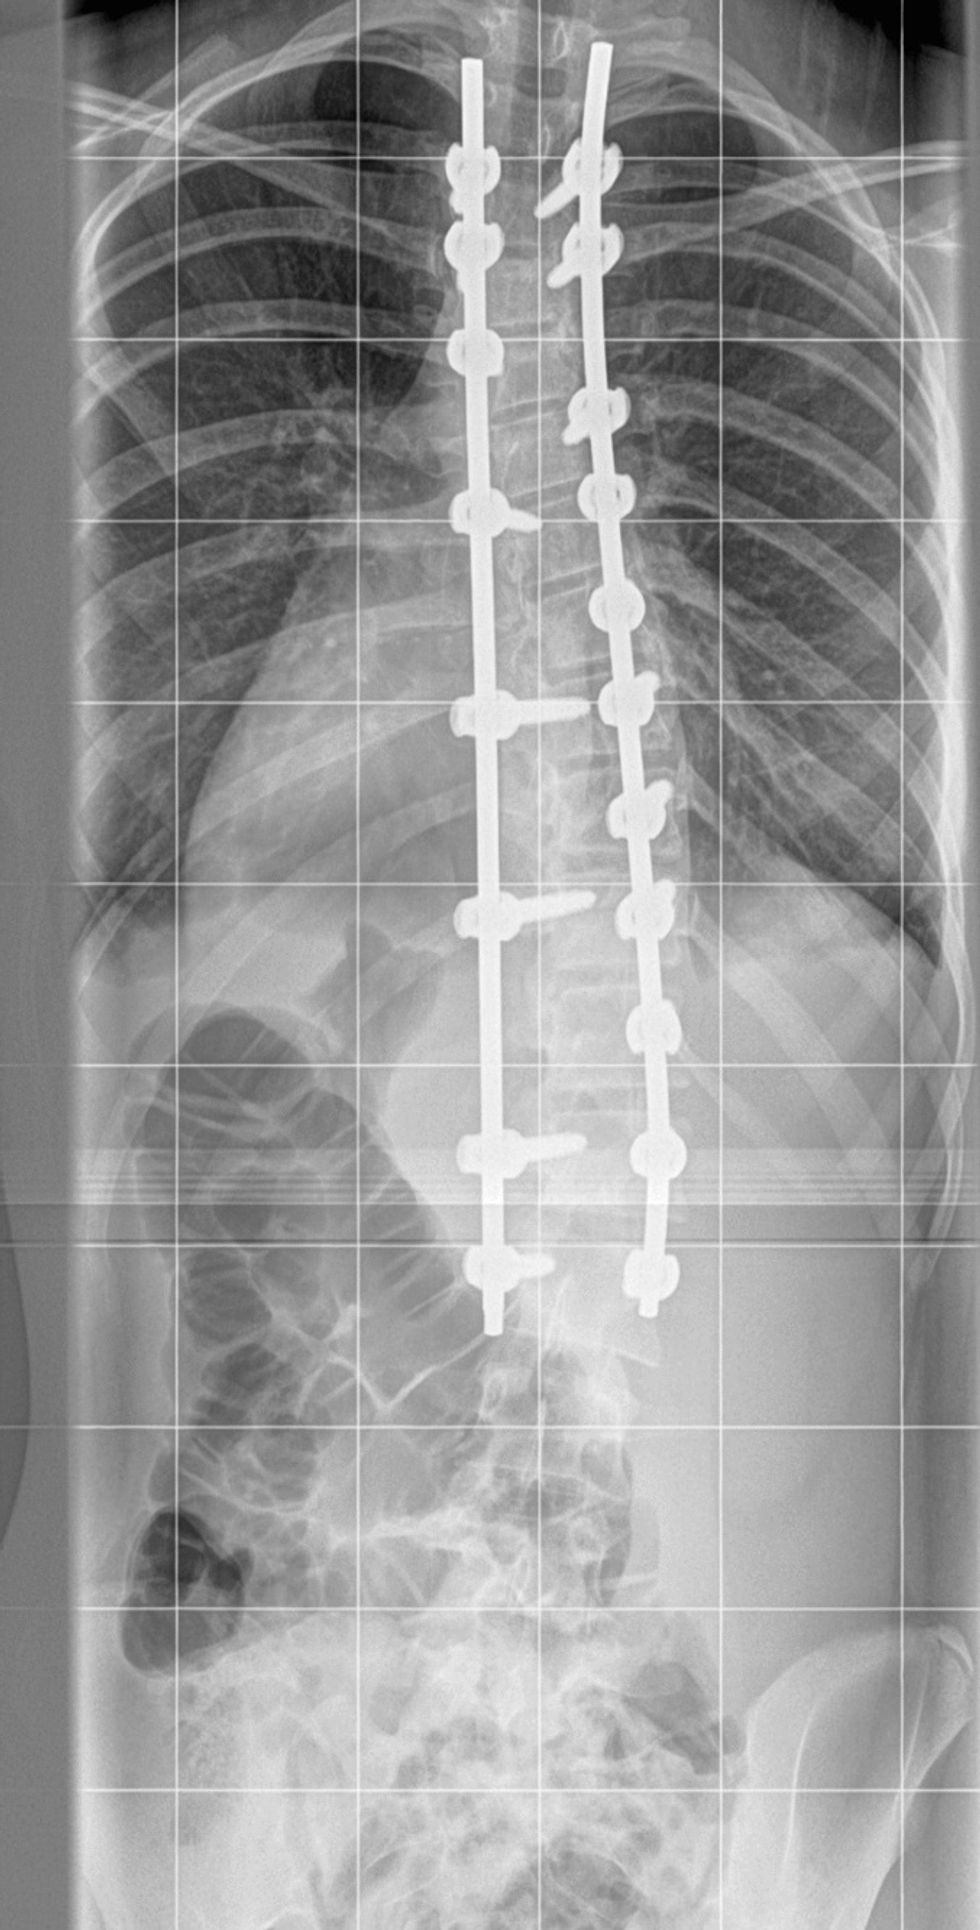

“Lily was really upset. We were told she needed a spinal fusion, to fuse the vertebrae, to correct any deformity."

“It involved six hours of surgery, with a week-long recovery period, during which she tried to take small steps daily and didn't go back to school until October."

“Nuffield Leeds were brilliant. The surgery by Mr. Almas Khan was scheduled really quickly and Lily was so brave."